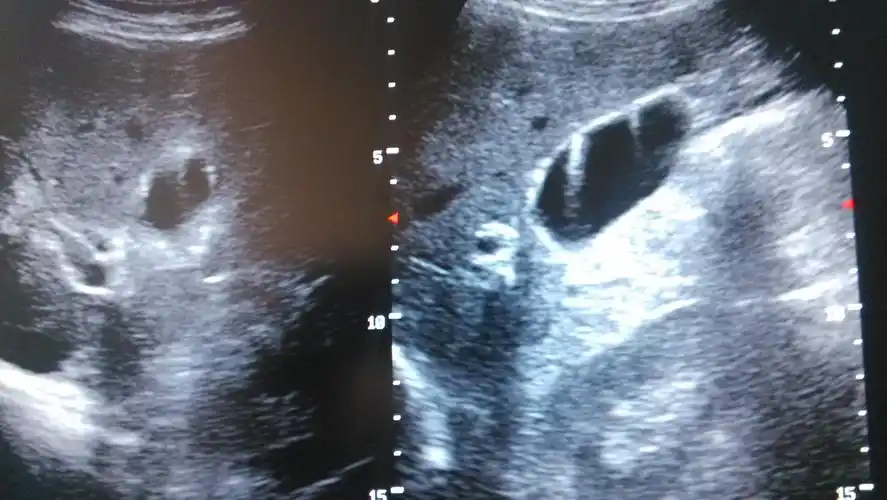

胆囊结石

每日技能影像学超声之胆囊结石

典型胆总管结石